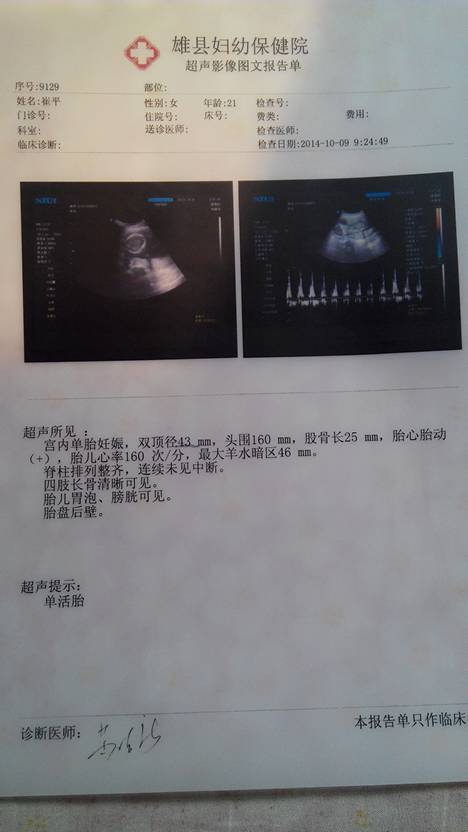

是男孩还是女孩,您可以做羊水穿刺术来却确定.建议您在怀孕16-20周是时候,去医院做羊水穿刺术,羊水穿刺术多在妊娠16~20周期间进行,通过羊膜穿刺术,采取羊水进行检查.检查项目包括细胞培养,性染色体鉴定,染色体核型分析,羊水甲胎蛋白测定,羊水生化检查等,以确定胎儿成熟程度和健康状况,诊断胎儿是否正...常或患有某些遗传病.对优生优育有重要的作用.通过羊水检查,可确定胎儿性别,并可间接诊断伴性遗传病,从而防止此类遗传病患儿的出生.